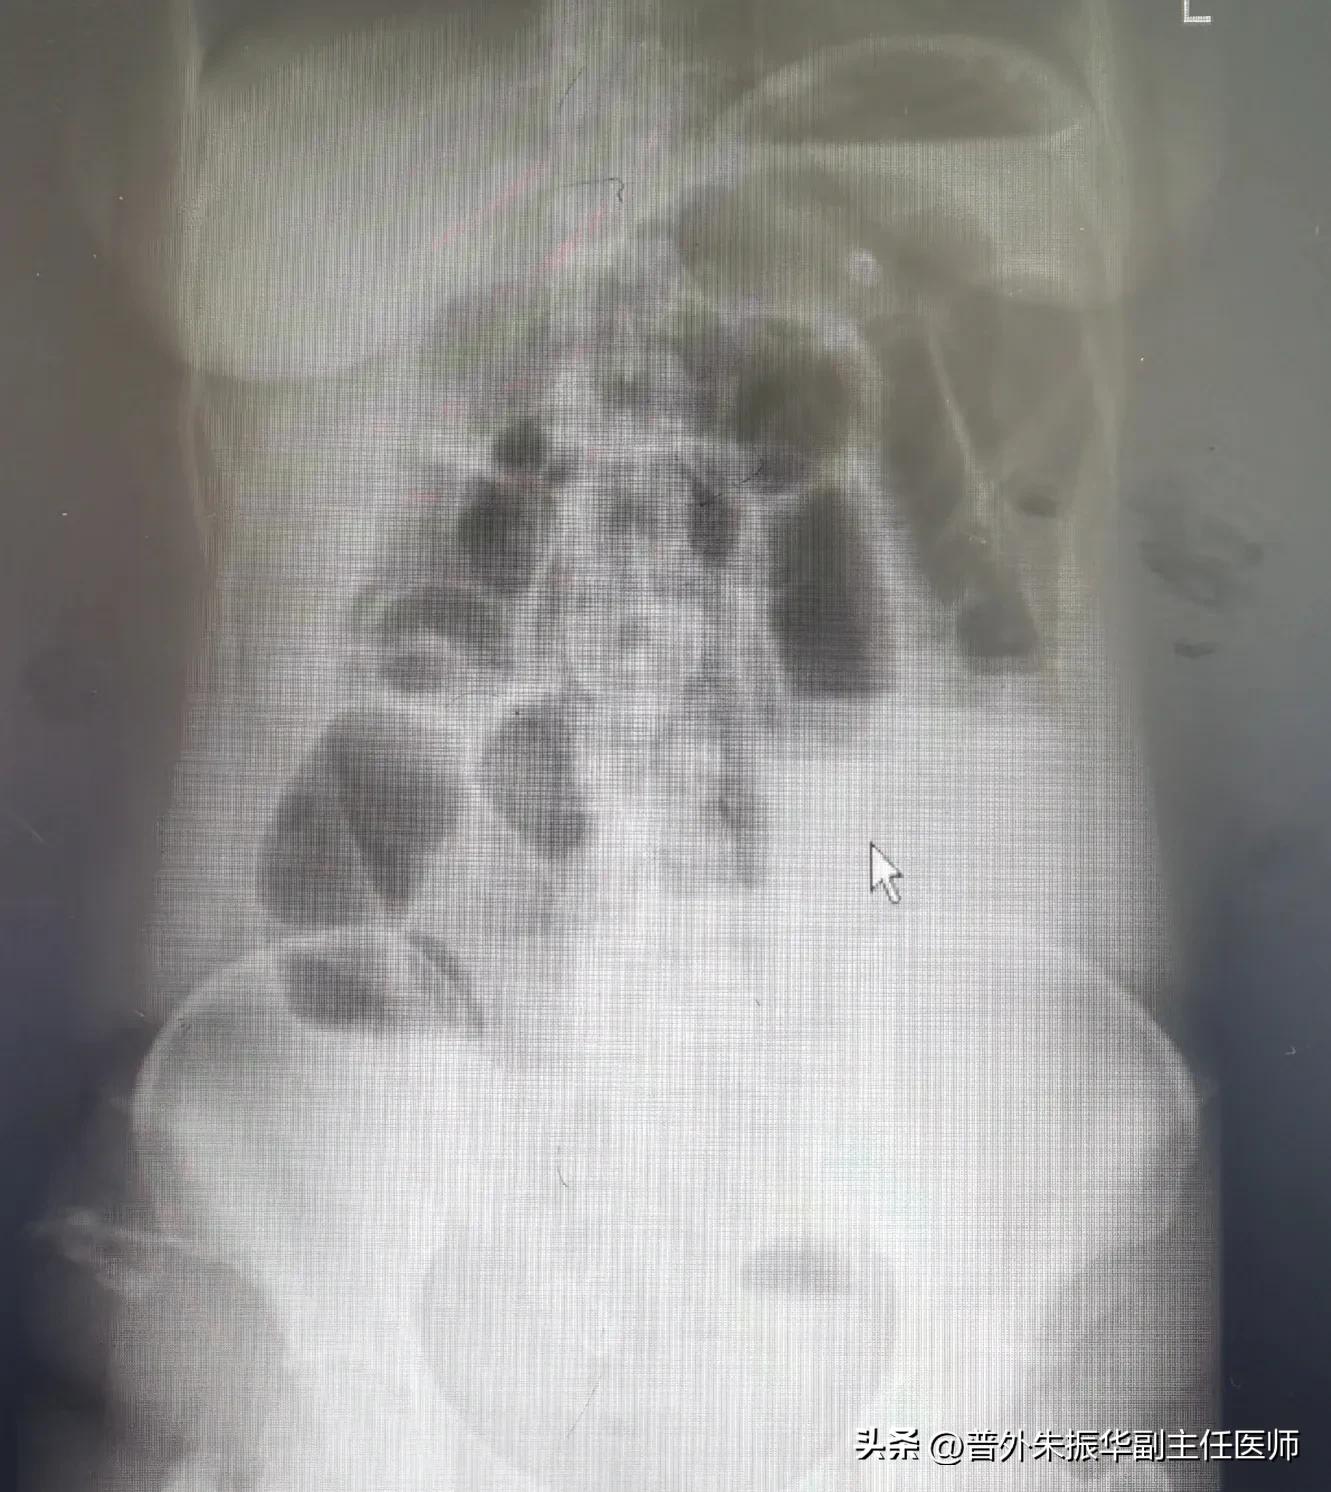

肠梗阻x线下表现

,其次肠系膜血管受压导致相应肠管血运障碍,严重者肠管绞窄坏死,不得不切除相应肠管。